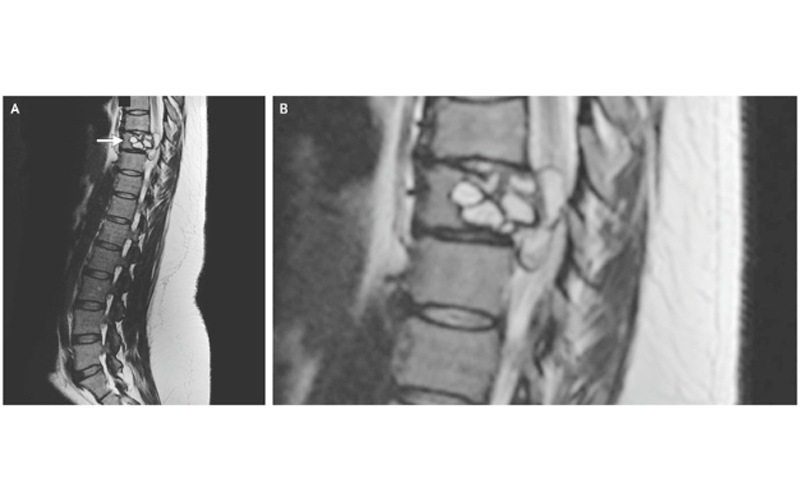

An MRI revealed tapeworm larval cysts in the woman’s spine, indicated by the arrow in the image on the left. The image on the right shows a close-up.

An MRI divulge a lesion on herspine , at her ninth thoracic vertebra , which is located in the middle of the back , the report said . [ 8 Awful Parasite Infections That Will Make Your Skin Crawl ]